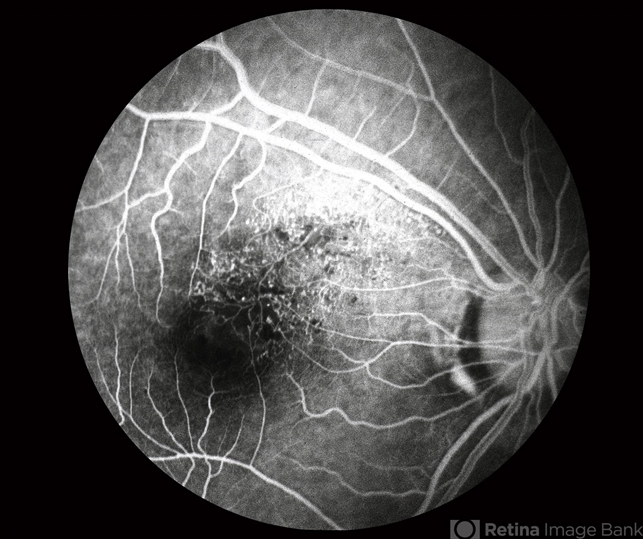

- early phase, branch retinal vein occlusion (BRVO), capillary nonperfusion, microaneurysms

- BRVO-FA early phase.